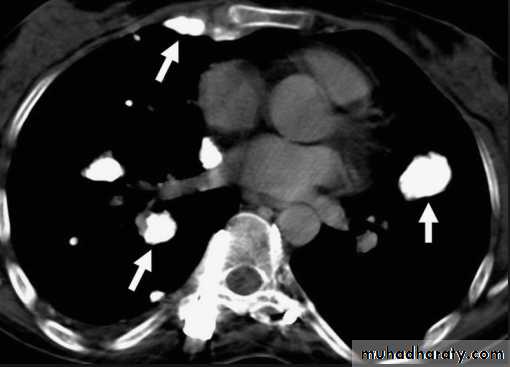

Sarcoid.

Marked lymphadenopathy (dotted lines) is seen in the region of both hila in the right paratracheal region (A).

The transverse contrast-enhanced computed tomography scan of the upper chest (B) clearly shows the ascending and descending aorta (Ao) as well as the pulmonary artery (PA) and superior vena cava. The right and left main-stem bronchus area also is seen. Arrows, the extensive lymphadenopathy.